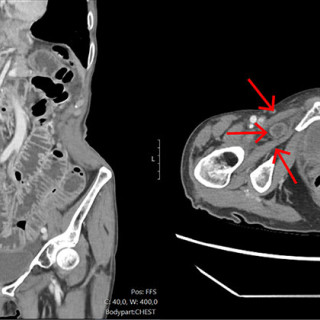

Denne kasuistikken beskriver alvorlig iatrogen botulisme etter behandling med injeksjon av botulinumtoksin ved en privatklinikk i utlandet. En kvinne i 40-årene ble akuttinnlagt i medisinsk avdeling grunnet økende svelgparese, svakhet i nakkemuskulatur, obstipasjon, munntørrhet, hodepine, fatigue, tunge øyelokk og uklart syn de siste fem dager. De siste tre dagene før innleggelsen hadde hun ikke fått i seg flytende eller fast føde, og hodet måtte støttes når hun skulle sette seg opp. Det fremkom at hun 15 dager tidligere hadde fått injisert botulinumtoksin type A mot migreneplager under et...